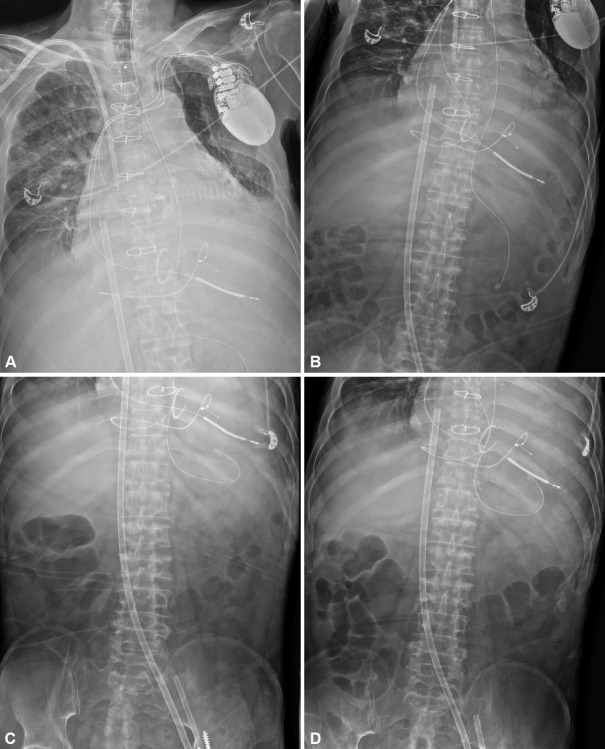

鼻胃管插入是一种常见的常规手术,用于各种目的。胃管引起的胃穿孔很少见,但可能危及生命。我们报告一个罕见的病例涉及延迟胃穿孔引起的胃管在成人终末期心力衰竭。

Nasogastric (NG) tube insertion is a common and routine procedure that is performed for various purposes. Gastric perforations caused by NG tubes are rare but potentially life-threatening. We report a rare case involving a delayed gastric perforation caused by an NG tube in an adult with end-stage heart failure.